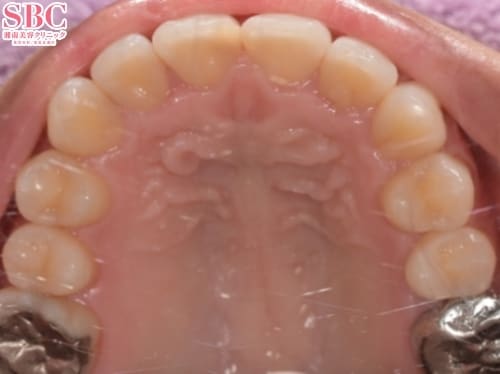

施術前

前歯のガタツキもそうですが、奥歯にもガタツキ強くあり、全体矯正のモデレートプランでご案内。

奥歯のアーチが狭く、当初は見える歯の本数が少なかったですが、